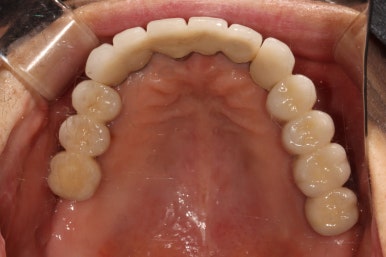

저희 치과와 협업하는 기공소에서 제작해온 임시치아를 장착한 상태입니다.

플라스틱 재질인 레진으로 제작되어 있어 색상은 그닥 수려하지 않으나, 연습용으로 써보기에는 아주 딱이죠?

생각보다 보기에 모양도 괜찮습니다. 요새 임플란트 보철물은 모두 CADCAM으로 지르코니아 블럭을 깎아서 제작하기 때문에, 만약 이 임시치아가 마음에 드셨다면 최종 지르코니아 크라운도 컴퓨터에 입력된 데이터를 이용하여 똑같이 깎아서 제작해드릴 수 있답니다. 이 모든게 치과에서 구강스캐너를 사용하기에 가능하죠..

어쨌든, 어금니 임플란트로 치아가 6개나 새로 제작되었기에 볼이나 혀가 씹히진 않는지 - 식사시에 아프거나 음식이 끼는 것은 없는지 등을 확인하기 위해 약 2-4주 정도 사용해보시게 됩니다.